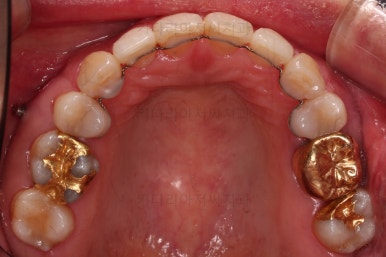

동래임플란트교정 마무리 되었습니다.

임플란트 머리도 잘 올라갔고, 치열도 가지런해졌으며 교합이나 중앙선도 적절히 마무리 되었습니다.